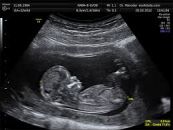

Siêu âm thai là một thủ thuật được thực hiện trong thai kỳ sử dụng sóng âm phản xạ. Nó tạo ra hình ảnh của thai nhi, cơ quan hỗ trợ thai nhi (nhau thai) và chất dịch bao quanh thai nhi (nước ối). Để hiểu rõ hơn về thủ thuật này, mời các bạn tham khảo bài viết dưới đây!